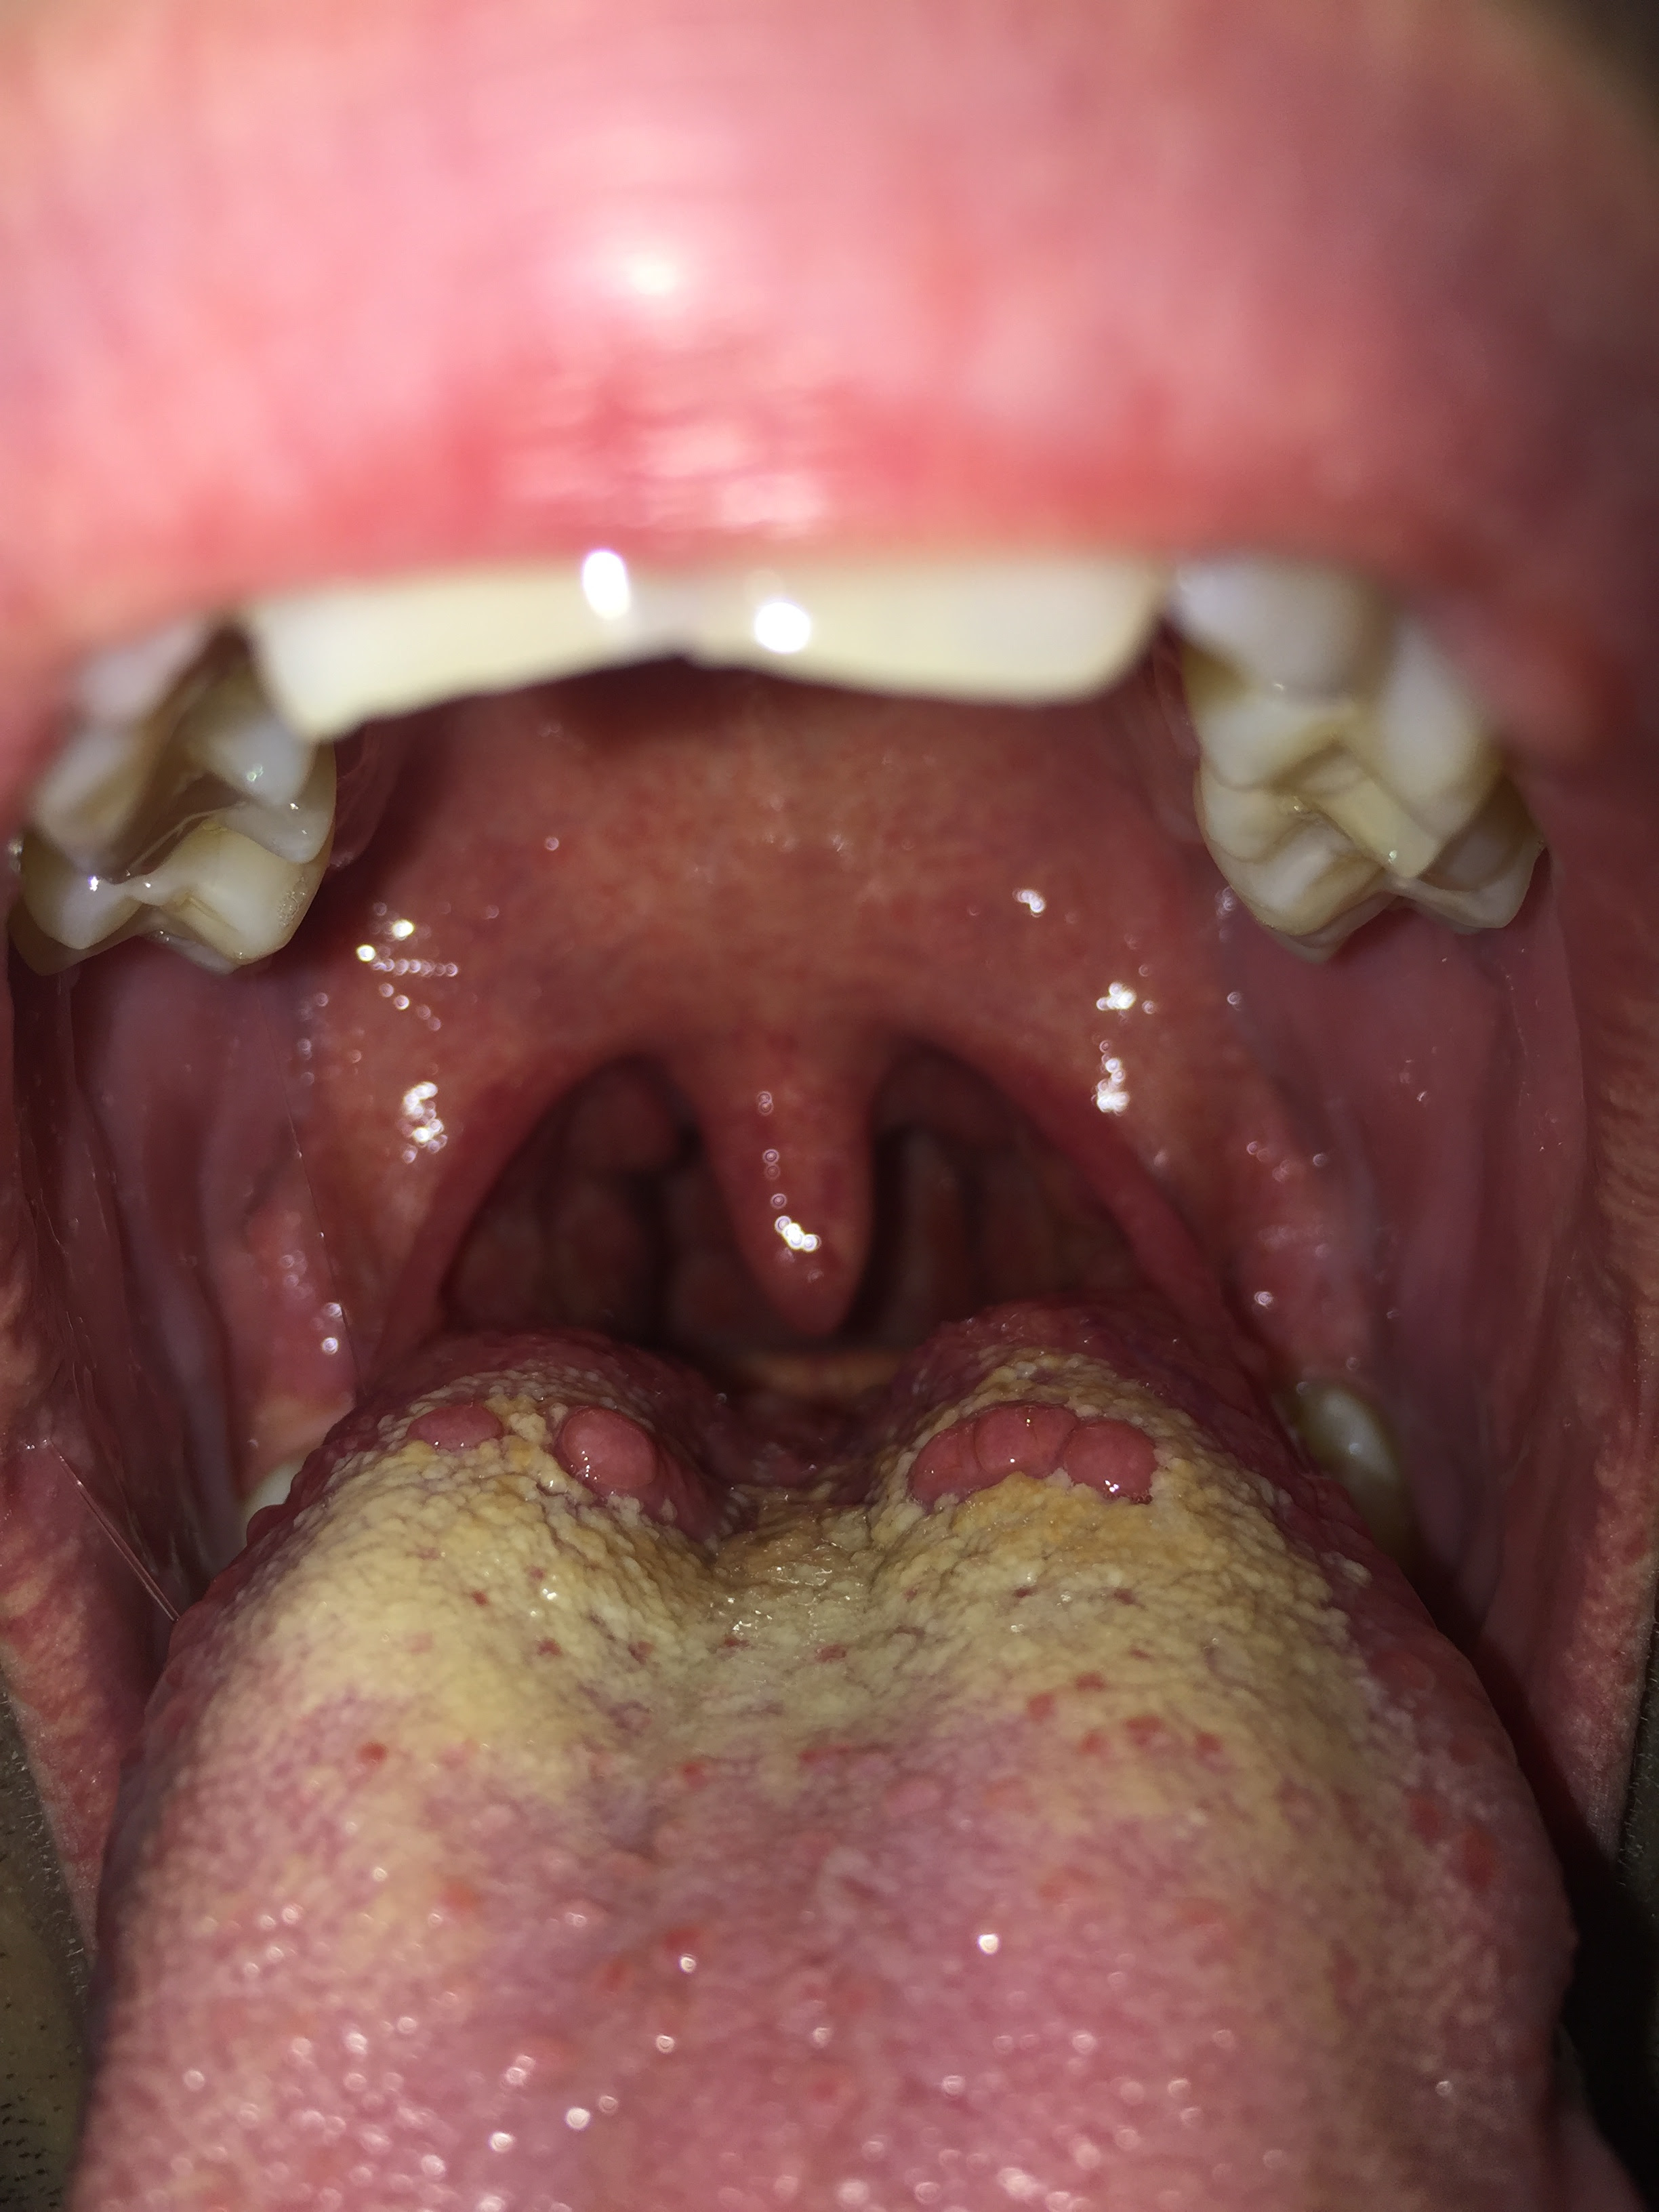

Pickel Auf Der Zunge / Pickel auf der Zunge - So wirst du es wieder los ... - Du bemerkst immer mal wieder pickel auf der zunge?. Möglicherweise haben sie gerade ein ohnehin geschwächtes immunsystem pickel auf der zunge sind zwar schmerzhaft, normalerweise aber kein grund zur besorgnis. Was sie bei sogenannten aphten tun können, erfahren sie in diesem beitrag. Leidet dein körper unter einem vitaminmangel, ist es auch nicht selten, dass dein. Da pickel auf der zunge bei jeder mundbewegsung schmerzen, ist eine schnelle behandlung unabdinglich. Sie werden oft eine beule auf der zunge finden, wenn es eine reizung oder entzündung der pilzförmigen.

Pickel im gesicht sind nichts neues, aber auch auf der zunge können sich pickel oder bläschen bilden. Dieser schmerzhafte gelbe pickel erscheint auf der zunge. Meist ist mangelnde hygiene der grund für pickel auf der zunge. Damit pickel auf der zunge entstehen können, gibt es viele verschiedene ursachen, welche von innen aber auch von außen kommen können. Mit gewöhnlicher akne haben sie wenig gemeinsam.

Wenn du bereits pickel auf der zunge hast, können einige einfache hausmittel zur linderung deiner symptome beitragen. Pickel auf der zunge können eine ganze reihe von ursachen haben. Also ich glaube es verwechseln hier ein paar leute was. Das früheste und wichtigste zeichen der glossitis ist zu taubheit und brennen bei der verwendung von heißen oder würzigen speisen betrachtet. Aber jede ähnliche bildung die menschen nennen es so. Eine der wichtigsten maßnahmen, um pickeln auf der zunge vorzubeugen, ist eine gesunde und ausgewogene ernährung. Dennoch sollten sie bei verdacht auf veränderung einen arzt aufsuchen. Dann muss hier erwähnt werden, dass sie falsch glauben, weil pickel nämlich zum beispiel auch unter. Pickel auf der zunge kommen in verschiedenen größen und farben vor pickel auf der rückseite der zunge kommen als rote, weiße, große oder kleine beulen vor. Die häufig rote blasen verursacht. Wer jetzt glaubt, aphthen auf der zunge entstehen wie pickel und pusteln im gesicht durch verstopfte talgdrüsen, liegt falsch. Du bemerkst immer mal wieder pickel auf der zunge? Normalerweise dient unsere zunge dazu, uns beim essen davor zu schützen, keine fremdkörper aufzunehmen.

Dazu gehören vor allem salbei und kamille. Ein schmerzhafter pickel auf der zunge wird auch als vorübergehende linguale papillitis bezeichnet. Die therapie reicht vom hausmittel bis hin zu tinkturen aus der apotheke. Die kleinen pusteln können sehr schmerzhaft sein, gerade wenn wir etwas säurehaltiges oder scharfes essen. Verfallen sie aber nicht gleich in panik, wenn sie einen pickel auf ihrer zunge haben. Mit gewöhnlicher akne haben sie wenig gemeinsam. Diese pickel erscheinen oft rot oder weiß, aber die farbe hängt stark von der ursache ab. Was sie bei sogenannten aphten tun können, erfahren sie in diesem beitrag. Eine der wichtigsten maßnahmen, um pickeln auf der zunge vorzubeugen, ist eine gesunde und ausgewogene ernährung. Aber jede ähnliche bildung die menschen nennen es so. Schnelle hilfe ist nun gefragt. Meist ist mangelnde hygiene der grund für pickel auf der zunge. Wie sehen pickel auf der zunge aus?

Pickel auf der zunge oder akne auf der zunge sind manchmal auf die reaktion bestimmter lebensmittel oder die einnahme toxischer chemikalien oder anderer allergien zurückzuführen. Ein schmerzhafter pickel auf der zunge wird auch als vorübergehende linguale papillitis bezeichnet. Die ursachen für die schmerzhaften zungenbläschen sind vielfältig: Auch wenn sie gelegentlich wie pickel auf der hautoberfläche aussehen. Oft sind sie schmerzhaft, prickeln und irritieren schlichtweg.